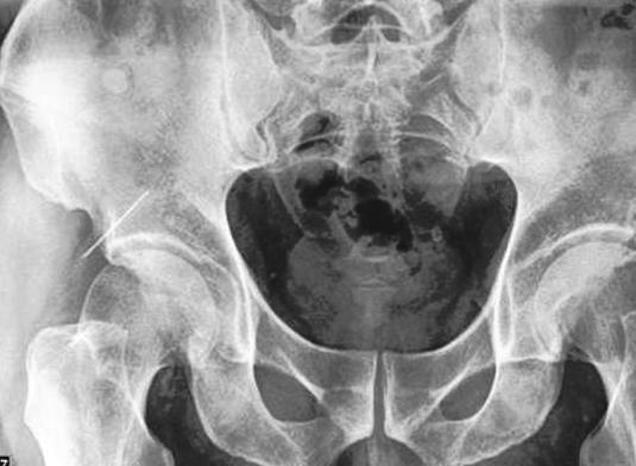

Akinek 40 éve beletörték a fenekébe az injekcióstűt a miskolci SZTK-ban, és a tű azóta is vándorol a testében, kiszedni pedig már nem lehet.

Dénes kálváriáját a Blikk már tavaly ismertette: annak idején azzal nyugtatták, hogy a tű majd magától kijön, de nem így történt. Az új fejlemény az, hogy most már örökre ott is marad: “Neves sebészek hosszas vizsgálódás után arra jutottak, hogy az időközben elvándorolt és a csontba fúródott tűt immár nem lehet kivenni az úr hátsó feléből.”

Azért döntöttek így, mert a tűt csak rendkívül bonyolult eljárással lehetne kivenni, amely számos veszéllyel járna, Dénes akár örök életére le is sántulhatna. Igaz, most meg a tű a csontba fúródva okoz komoly fájdalmakat, és Dénest csak az vigasztalhatja kicsit, hogy maradandó egészségkárosodás miatt komoly kártérítést kaphat a műhibát vétő intézmény jogutódjától.